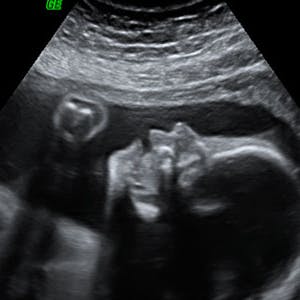

Gravid

Vi gør en dyd ud af at klæde dig godt på både før, under og efter din graviditet. Vi ved, at der kan komme mange spørgsmål til din graviditet, fødsel, amning, din babys udvikling og mange flere emner, derfor har vi samlet guides, tips & tricks samt læsernes egne fortællinger i dette gravid univers.